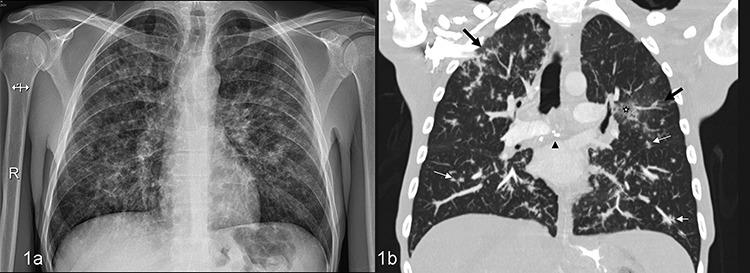

Role of chest CT in concomitant pulmonary TB and Kaposi sarcoma in a HIV patient.